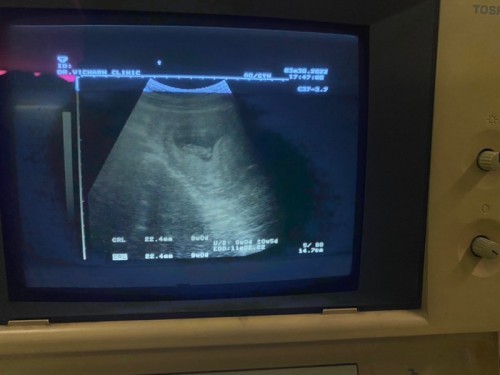

ท้องได้10สัปดาห์ค่ะ นอนอยู่เเล้วเอี้ยวตัวไปทางขวาจะหยิบหมอน เเล้วรู้สึกเสียวท้อง เจ็บท้องจี๊ดดดเลย 1 ครั้ง อันตรายมั้ยค่ะ รู้สึกกังวล เเม่ๆคนไหนเคยเป็นบ้างค่ะ